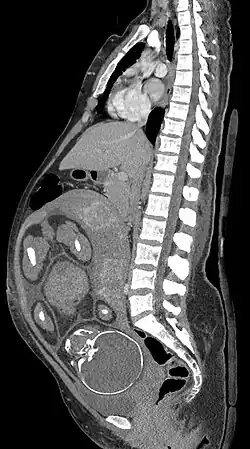

Median plane CT scan of a pregnant woman. The fetus (exposed in the coronal plane) is 37 weeks of gestational age.